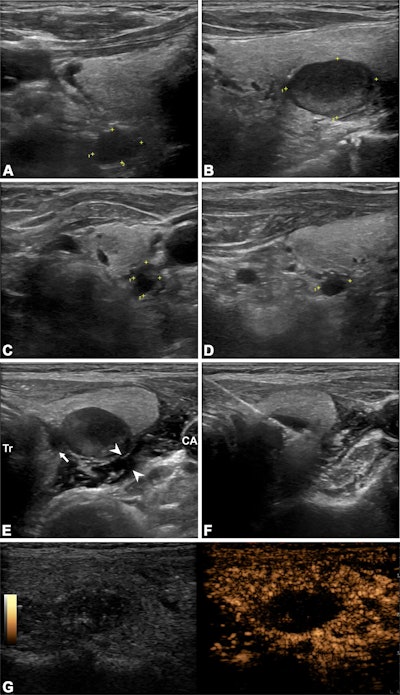

Ultrasound images depict a 63-year-old man who underwent radiofrequency ablation (RFA) for the treatment of secondary hyperparathyroidism. (A–D) 2D images show four hyperplastic parathyroid glands on the right and left sides (marked with crosshairs). The numbers near the crosshairs represent the number of measured trails. (E) Ultrasound-guided infusion of isolation fluid (arrowheads) around the hyperplastic parathyroid gland to protect vital organs such as the trachea (Tr), carotid arteries (CA), and recurrent laryngeal nerve pathway area (arrow). F) Ultrasound-guided RFA of the hyperplastic parathyroid gland. (G) Immediate postoperative contrast-enhanced ultrasound shows no contrast enhancement in the ablation area. The ablation procedures for the other three parathyroid glands were the same as those described above. Image courtesy of the RSNA,